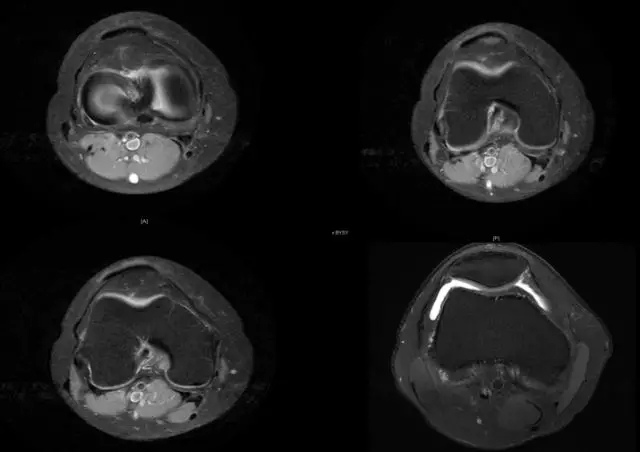

正常的膝关节

韧带结构:形态,张力,质地,连续性

半月板:完整性,形态,质地

Blumensaat 角(-1.6度)

大于9-15度视为异常

前交叉韧带与胫骨平台角度(56度)

小于45-50度视为异常

后交叉韧带折弯度

弧度:0.19厘米,角度:114-123度